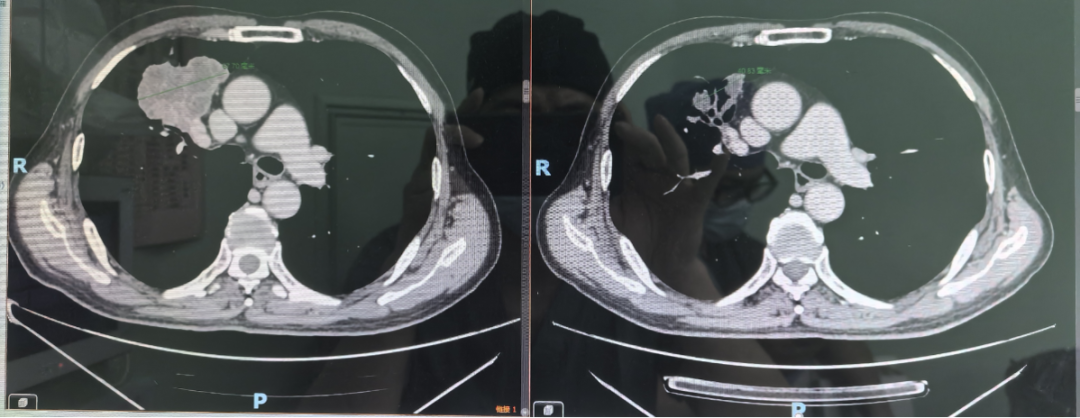

本以为是做进一步病情分析,但“片子”出来后,医生发现了新“bug”——肺上还有肿块。

后续的检查显示:老周食管癌和肺癌双原发癌晚期!

不过,黄楚坚医生指出,像老周这样,食管癌合并其他原发性癌症不是很常见。“一百个食管癌患者里,大概只有一两个合并肺癌的。像老周这样,两个原发癌都是局部晚期,确实不好治。”

其食管癌由于发现较晚,已经到达了晚期阶段,且与肺癌并存,这大大增加了治疗的复杂性。

化疗一个周期后,原本咽不下东西只能吃流食的老周,再一次享受到“干饭”的快乐。又经过两个新辅助治疗周期后,检查发现肺部肿瘤缩小了50%,食管肿瘤也缩小了很多,医生告诉老周可以手术了。